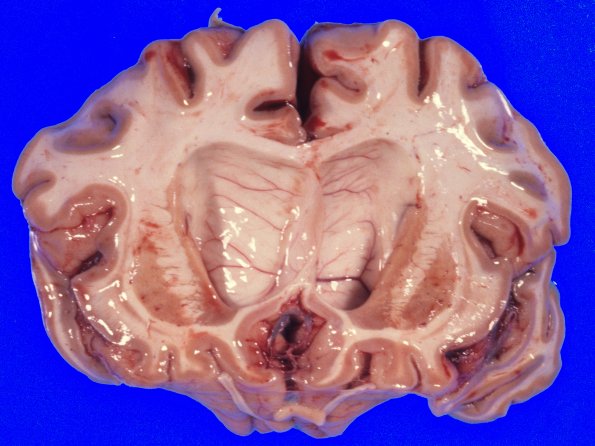

Coronal sections of the right cerebral hemisphere confirm the significant degree of cortical atrophy involving the frontal lobes and parietal lobes. The deep gray nuclei are remarkable for an almost total collapse of the head of the caudate nucleus which appears as a thin orange-stained band in the lateral aspect of the extensively dilated lateral ventricle. The superior and anterior aspect of the caudate head are most extensively involved; the inferior aspect merging into the substantia innominata appears less extensively involved. The normal convex outlines of the head of the caudate are now concave. Adjacent areas of the internal capsule appear unremarkable.